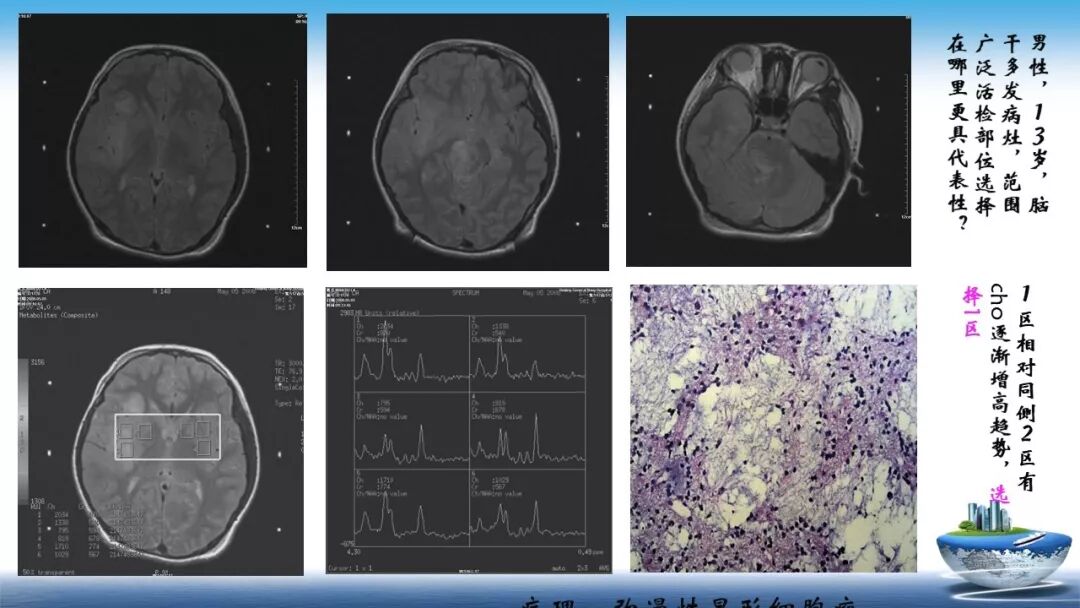

立体定向活检在脑干中线病变精准诊断中的作用

今天为大家带来的是中国人民解放军总医院第六医学中心(原中国人民解放军海军总医院)王亚明、于新、张剑宁带来的精彩课题分享:立体定向活检在脑干中线病变精准诊断中的作用,欢迎观看、阅读!